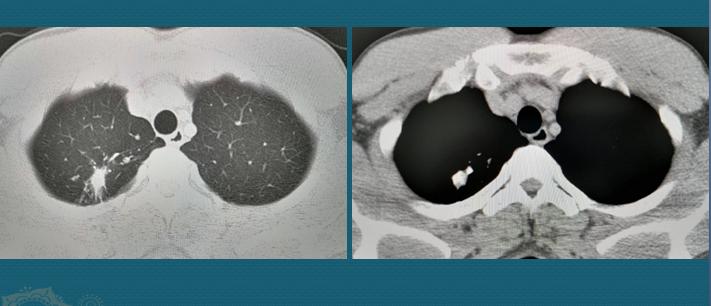

肺结核结节发生钙化、肺内残留索条影、胸膜钙化、长期稳定的净化性空洞,或空洞内内容物钙化,稳定的支气管残留损伤(如支气管扭曲、扩张)等,提示肺结核处于稳定期。

像这位病人36岁,右肺尖结节灶,大部分钙化,周围有少量纤维灶和微结节灶,随访观察2年无任何变化,是陈旧性结核灶,稳定期,不需要治疗了。